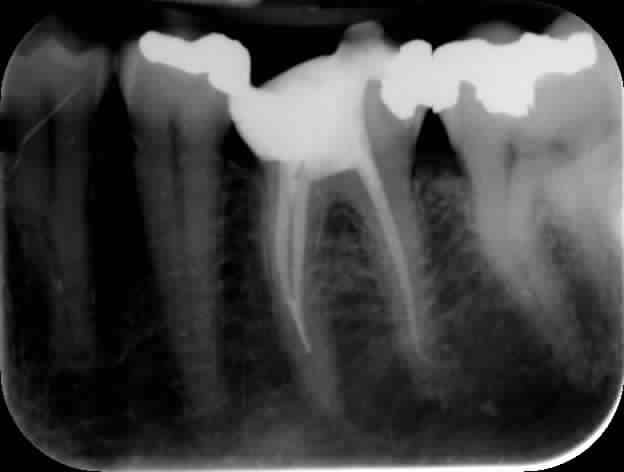

y avait quoi comme pathologie à la base?

(tu peux pas améliorer la qualité de ta radio?)

Le patient avait des signes de pulpite irréversible.

Je suis désolé mais je ne sais pas comment améliorer la qualité de l'image. Je ne sais pas quel format de compression je peux utiliser sur eugénol. Le BMP proposé par mudem ne passe pas.